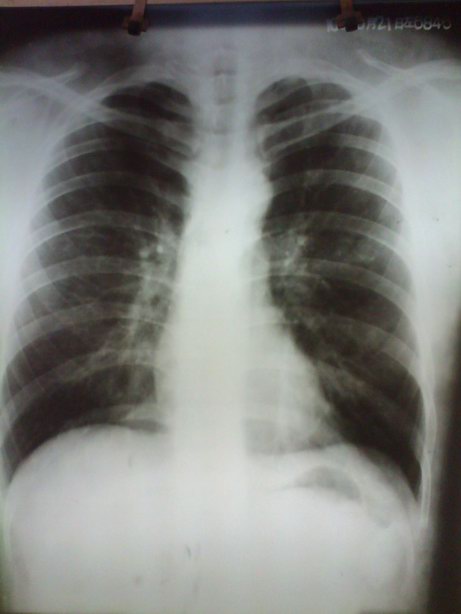

标题: X8070:考虑左侧肺底积液对吗???? [打印本页]

标题: X8070:考虑左侧肺底积液对吗????

男。20岁。咳嗽10天余。

左膈最高点偏外1/3,胃底与膈顶间距增大,不除我左肺底积液,建议变换体位(左侧倾斜60度)透视观察。

胃泡肺底间距增宽,超过2cm,提示左侧肺底积液。

支持考虑左肺底积液。

膈肌外侧较高可提示肺底积液,结合透视观察。

胃泡膈顶间距增宽,但膈肌形态尚可,不支持肺底积液,不敢肯定,建议结合透视观察。